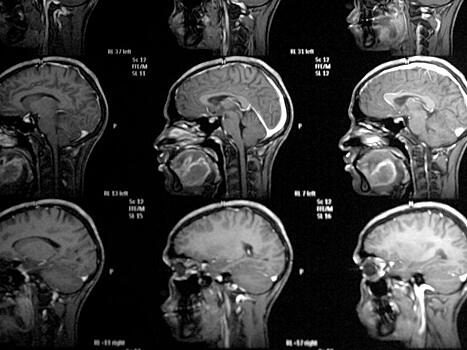

Ученые научились заменять поврежденные клетки мозга

Исследователи надеются получить возможность заменять дисфункциональные клетки мозга.

Новое исследование ученых из Каролинского института в Стокгольме поддерживает теорию о возможной замене дисфункциональных иммунных клеток в мозге. Данная методика обладает громадным терапевтическим потенциалом при таких нейродегенеративных расстройствах, как болезнь Альцгеймера или боковой амиотрофический склероз (БАС). Исследование включало восстановление популяции в мозге новых иммунных клеток при экспериментальной модели болезни.

Речь идет о макрофагах, или иммунных клетках, которые присутствуют в нашем организме. Их «специализация» зависит от того органа, внутри которого клетки находятся. В мозге эти клетки известны под именем микроглии. В здоровом мозге микроглии вовлечены во множество специфических функций вроде поддержки активности и здоровья нервных клеток. При таких болезнях, как БАС или старческое слабоумие, микроглии начинают повреждать нервные клетки.

Авторы исследования считают, что замена дисфункциональных микроглий здоровыми клетками окажет потенциально терапевтическое воздействие при борьбе с развитием тяжелых и неизлечимых нейродегенеративных болезней. Именно поэтому они и создали новую модель болезни, в которой собственные микроглии животного удалялись из центральной нервной системы. Это привело к быстрому притоку моноцитов — прекурсоров макрофагов — в мозг и позвоночник. Впоследствии данная ситуация поспособствовала стремительному развитию новых похожих на микроглии клеток.